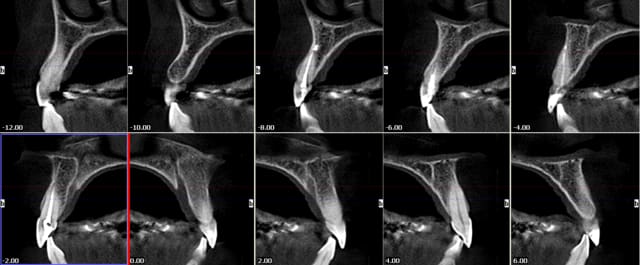

Bon finalement j'ai fait mon choix, cone beam installé hier !

Vatech Ewoo.

Pour moi les plus :

- taille de champ variable: 5*5 8*5 8*8 12.5*8

- vraie combo pano/cone beam

- interface sympa

- artefact métallique limité

- Logiciel d'imagerie et planification implantaire très bien

(pour info c'est une version d'Ondemand3D à l'essaie pour 90j ici:

http://www.ondemand3d.com/Content/Download/Trial.aspx prix du soft environ 5000$)

- budget compétitif

quelques clichés d'essais

chatondecarte

30/04/2010 à 00h56

justement celui que je veux prendre!

C'est le duo3D?

Tu peux mettre une coupe de zone molaire en gros plan pour voir si on voit bien le canal mandibulaire?